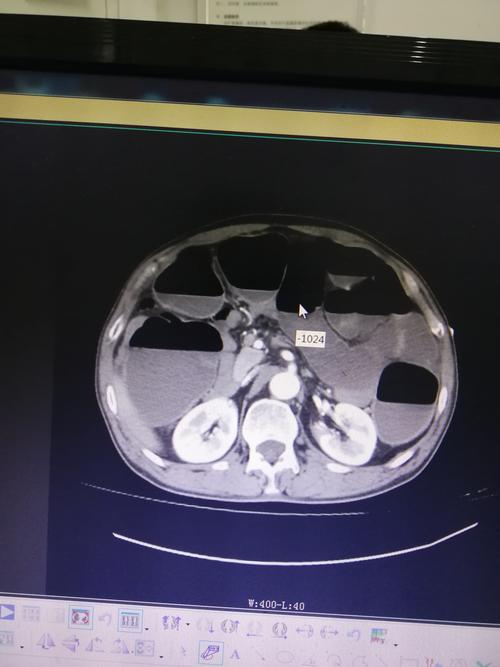

门诊dr腹部立位片提示:肠管积气,多个气液平面.

入院检查见立位腹部平片阶梯排列的气液平面.

肠梗阻为什么会出现气液平面

气液平面x线图片

气液平面